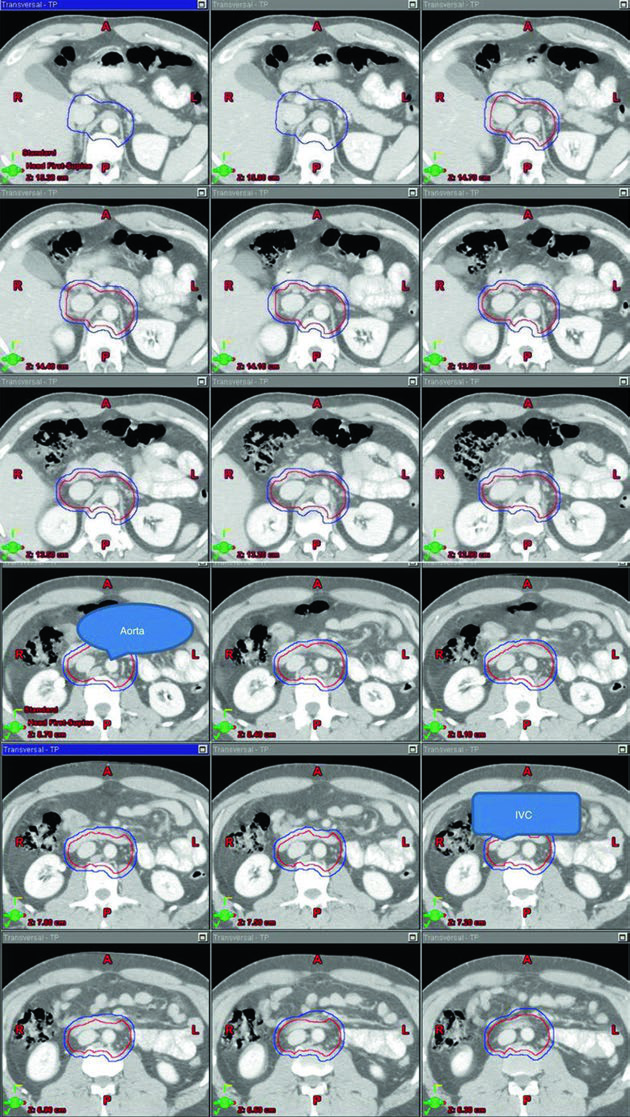

As figuras do capítulo ajudam porque mostram o volume organizado sobre a anatomia vascular, não apenas como um desenho abstrato. Na sequência superior-inferior do estágio I, o leitor enxerga como cava inferior e aorta funcionam como eixo geométrico do contorno, e isso conversa diretamente com a tabela de volumes. O valor dessa apresentação está em ligar cartografia linfonodal, marcos anatômicos e limites de bloco em uma mesma lógica.

O CTV do estágio I parte do contorno da cava inferior e da aorta desde 2 cm abaixo do topo do rim, superiormente, até a bifurcação dos vasos ilíacos, inferiormente. Depois, a cava recebe expansão de 1,2 cm e a aorta recebe expansão de 1,9 cm. Os dois volumes são combinados, e então se subtraem osso, músculo e alça intestinal. Esse detalhe é importante porque mostra que o capítulo não descreve apenas “onde cobrir”, mas também onde recuar para respeitar anatomia normal. Na sequência, o volume final é expandido em 0,5 cm mais 0,7 cm até a borda do bloco para formar o PTV.

Os marcos anatômicos completam a definição. O limite superior fica no topo de T11, com observação de que algumas fontes recomendam topo de T12. O limite inferior fica na base de L5. Lateralmente, o campo vai até a borda dos processos transversos, tipicamente em largura de cerca de 10 cm. Para seminoma à esquerda, os estudos de mapeamento nodal citados no capítulo sugerem que cobrir o hilo renal esquerdo pode ser opcional. Esse “pode ser opcional” é o tipo de nuance que vale ouro: não é omissão, é escolha deliberada ancorada em topografia.

| Volume-alvo | Definição baseada em TC e anatomia vascular | Definição baseada em marcos anatômicos |

|---|---|---|

| CTV | Contornar cava inferior e aorta desde 2 cm abaixo do topo do rim, superiormente, até a bifurcação dos vasos ilíacos, inferiormente. Expandir a cava inferior em 1,2 cm e a aorta em 1,9 cm. Combinar os dois volumes e subtrair osso, músculo e intestino. |

Borda superior: topo de T11 (algumas fontes recomendam topo de T12) [6]. Borda inferior: base de L5. Bordas laterais: margem dos processos transversos, tipicamente cerca de 10 cm de largura. |

| PTV 20–25,5 Gy em 1,5–2,0 Gy por fração |

Expandir o CTV final em 0,5 cm + 0,7 cm até a borda do bloco. | Para seminoma à esquerda, os estudos de mapeamento nodal sugerem que cobrir o hilo renal esquerdo é opcional [7]. |

O ponto técnico mais útil é que o dogleg não nasce do zero. Ele começa com o mesmo contorno de cava inferior e aorta usado no estágio I e, em seguida, incorpora vasos ilíacos comuns, porções proximais dos ilíacos internos até a emergência da glútea superior e vasos ilíacos externos até a borda superior do acetábulo, com expansão de 1,2 cm respeitando limites anatômicos. Depois disso, o capítulo pede contorno da doença nodal grosseira, o GTV, com expansão de 0,8 cm respeitando a anatomia, formando um CTV nodal. A união do CTV vascular com o CTV nodal produz o CTV inicial.